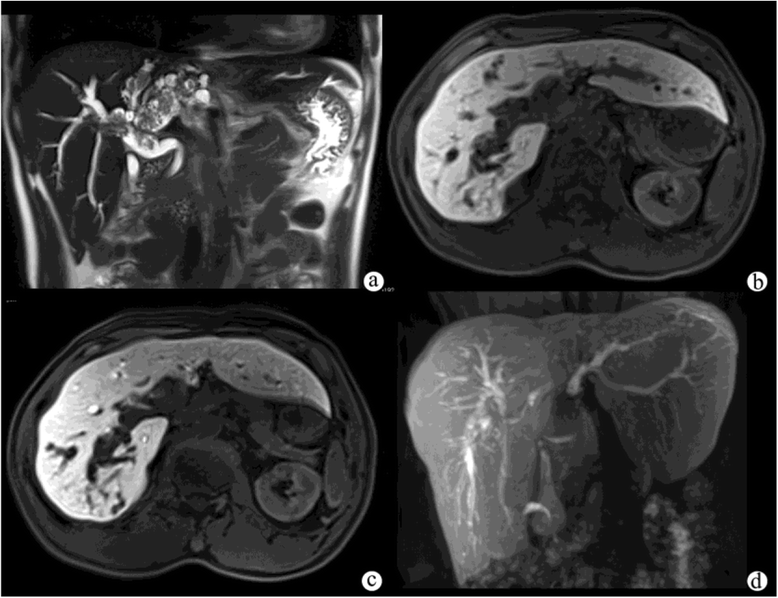

Figure 3 from Respiratory motion artefacts in GdEOBDTPA (Primovist

Figure 3 from Respiratory motion artefacts in GdEOBDTPA (Primovist Mri And Eovist eovist is indicated for intravenous use in magnetic resonance imaging (mri) of the liver to detect and characterize lesions in. gadoxetic acid (gadolinium ethoxybenzyl diethylenetriamine pentaacetic acid [eovist or primovist; This agent is becoming increasingly important for detecting and characterizing lesions in patients known or suspected to have hepatic mass. eovist ® (gadoxetate disodium) injection is indicated. Mri And Eovist.